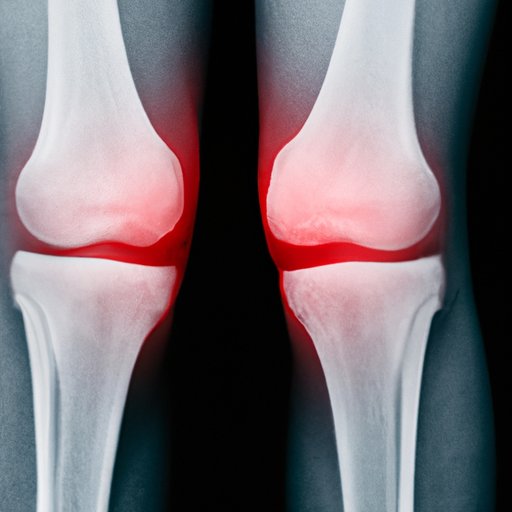

Nerve damage occurs when the nerves that send signals to and from your brain and spinal cord are injured or damaged. When this happens in the knee, it can cause a range of symptoms, including pain, numbness, tingling, and muscle weakness. It’s important to differentiate these symptoms from other knee problems, such as arthritis or injury, to properly diagnose and treat nerve damage.

Let’s dive deeper into each symptom of nerve damage in the knee and explain what it feels like and why it happens. Pain is a common symptom of nerve damage and can feel like a sharp or shooting pain, a burning sensation, or a dull ache. Numbness is another symptom that occurs when you lose sensation in your knee or leg. Tingling, on the other hand, can feel like pins and needles or a prickling sensation. Muscle weakness can also occur as a result of nerve damage, making it difficult to support your body weight or walk properly.